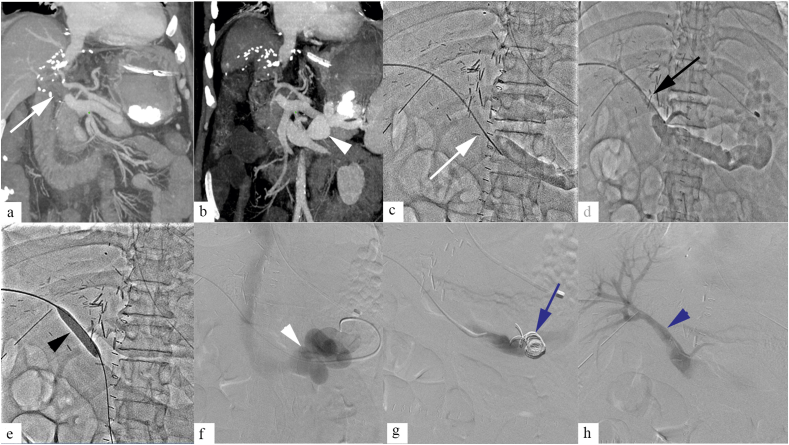

Figure 3.

A 33-month-old male child presenting with liver function abnormality, a year after liver transplantation. Contrast enhanced CT (a), and DSA (b, c) showed portal vein stenosis (PVS) (white arrow) at the site of anastomosis. Balloon angioplasty was done for PVS (d, e, black arrow). Postprocedure angiogram showed good flow across the anastomotic site (f, white arrowhead).

Figure 4.

A 46-year-old female patients presenting with variceal bleeding, 8 months following liver transplantation. Contrast enhanced CT abdomen (a), and venogram (b) showed portal vein stenosis at the site of anastomosis (white arrow). Primary stenting was done (c, black arrow), following which good flow was noted with in the portal vein across the anastomosis (d, back arrowhead).

Asymptomatic patients with normal LFT can be managed conservatively. Endovascular management is treatment of choice in symptomatic patients with PVS, with high success rate, and low complication risk.4,6 Transstenotic pressure gradient of >3–5 mmHg is considered significant.31,32 Angioplasty is often the first line of management (Figure 3). Both transjugular or transhepatic approach are commonly used. Size of the balloon depends on size of the normal portal vein segment. End point of angioplasty is when there is no significant residual stenosis and significant reduction of transstenotic gradient. A study by Saad et al. reported 82% 5 year patency rate in angioplasty group, and 100% in the stent group.33 While primary stenting is associated with high patency rate (Figure 4), stenting is often reserved for patients with incomplete response to angioplasty or restenosis, as stent within portal vein can hinder retransplantation if required, and progressive stenosis can be seen in pediatric patients with increase in age.4,6 Self-expandable stent of size same as or ∼10–20% greater than prestenotic segment is commonly used. In pediatric patients, short length balloon expandable stent of size >7–8 mm is often preferred because they can be accurately positioned.34 Though there is no consensus regarding periprocedural anticoagulation, systemic anticoagulation is generally recommended following angioplasty. INR is maintained between 2 and 3. In our practice, unfractionated heparin is initially used for anticoagulation with close monitoring of coagulation parameters. This is followed by low molecular weight heparin. Subsequently, depending upon the patency, portal flow, and. platelet count, the maintenance anticoagulation is prescribed. DUS is performed every 1–3 months posttransplant. CT angiography is done when abnormality is suspected on DUS. Surgical revision or retransplantation for PVS is rarely required.4,6